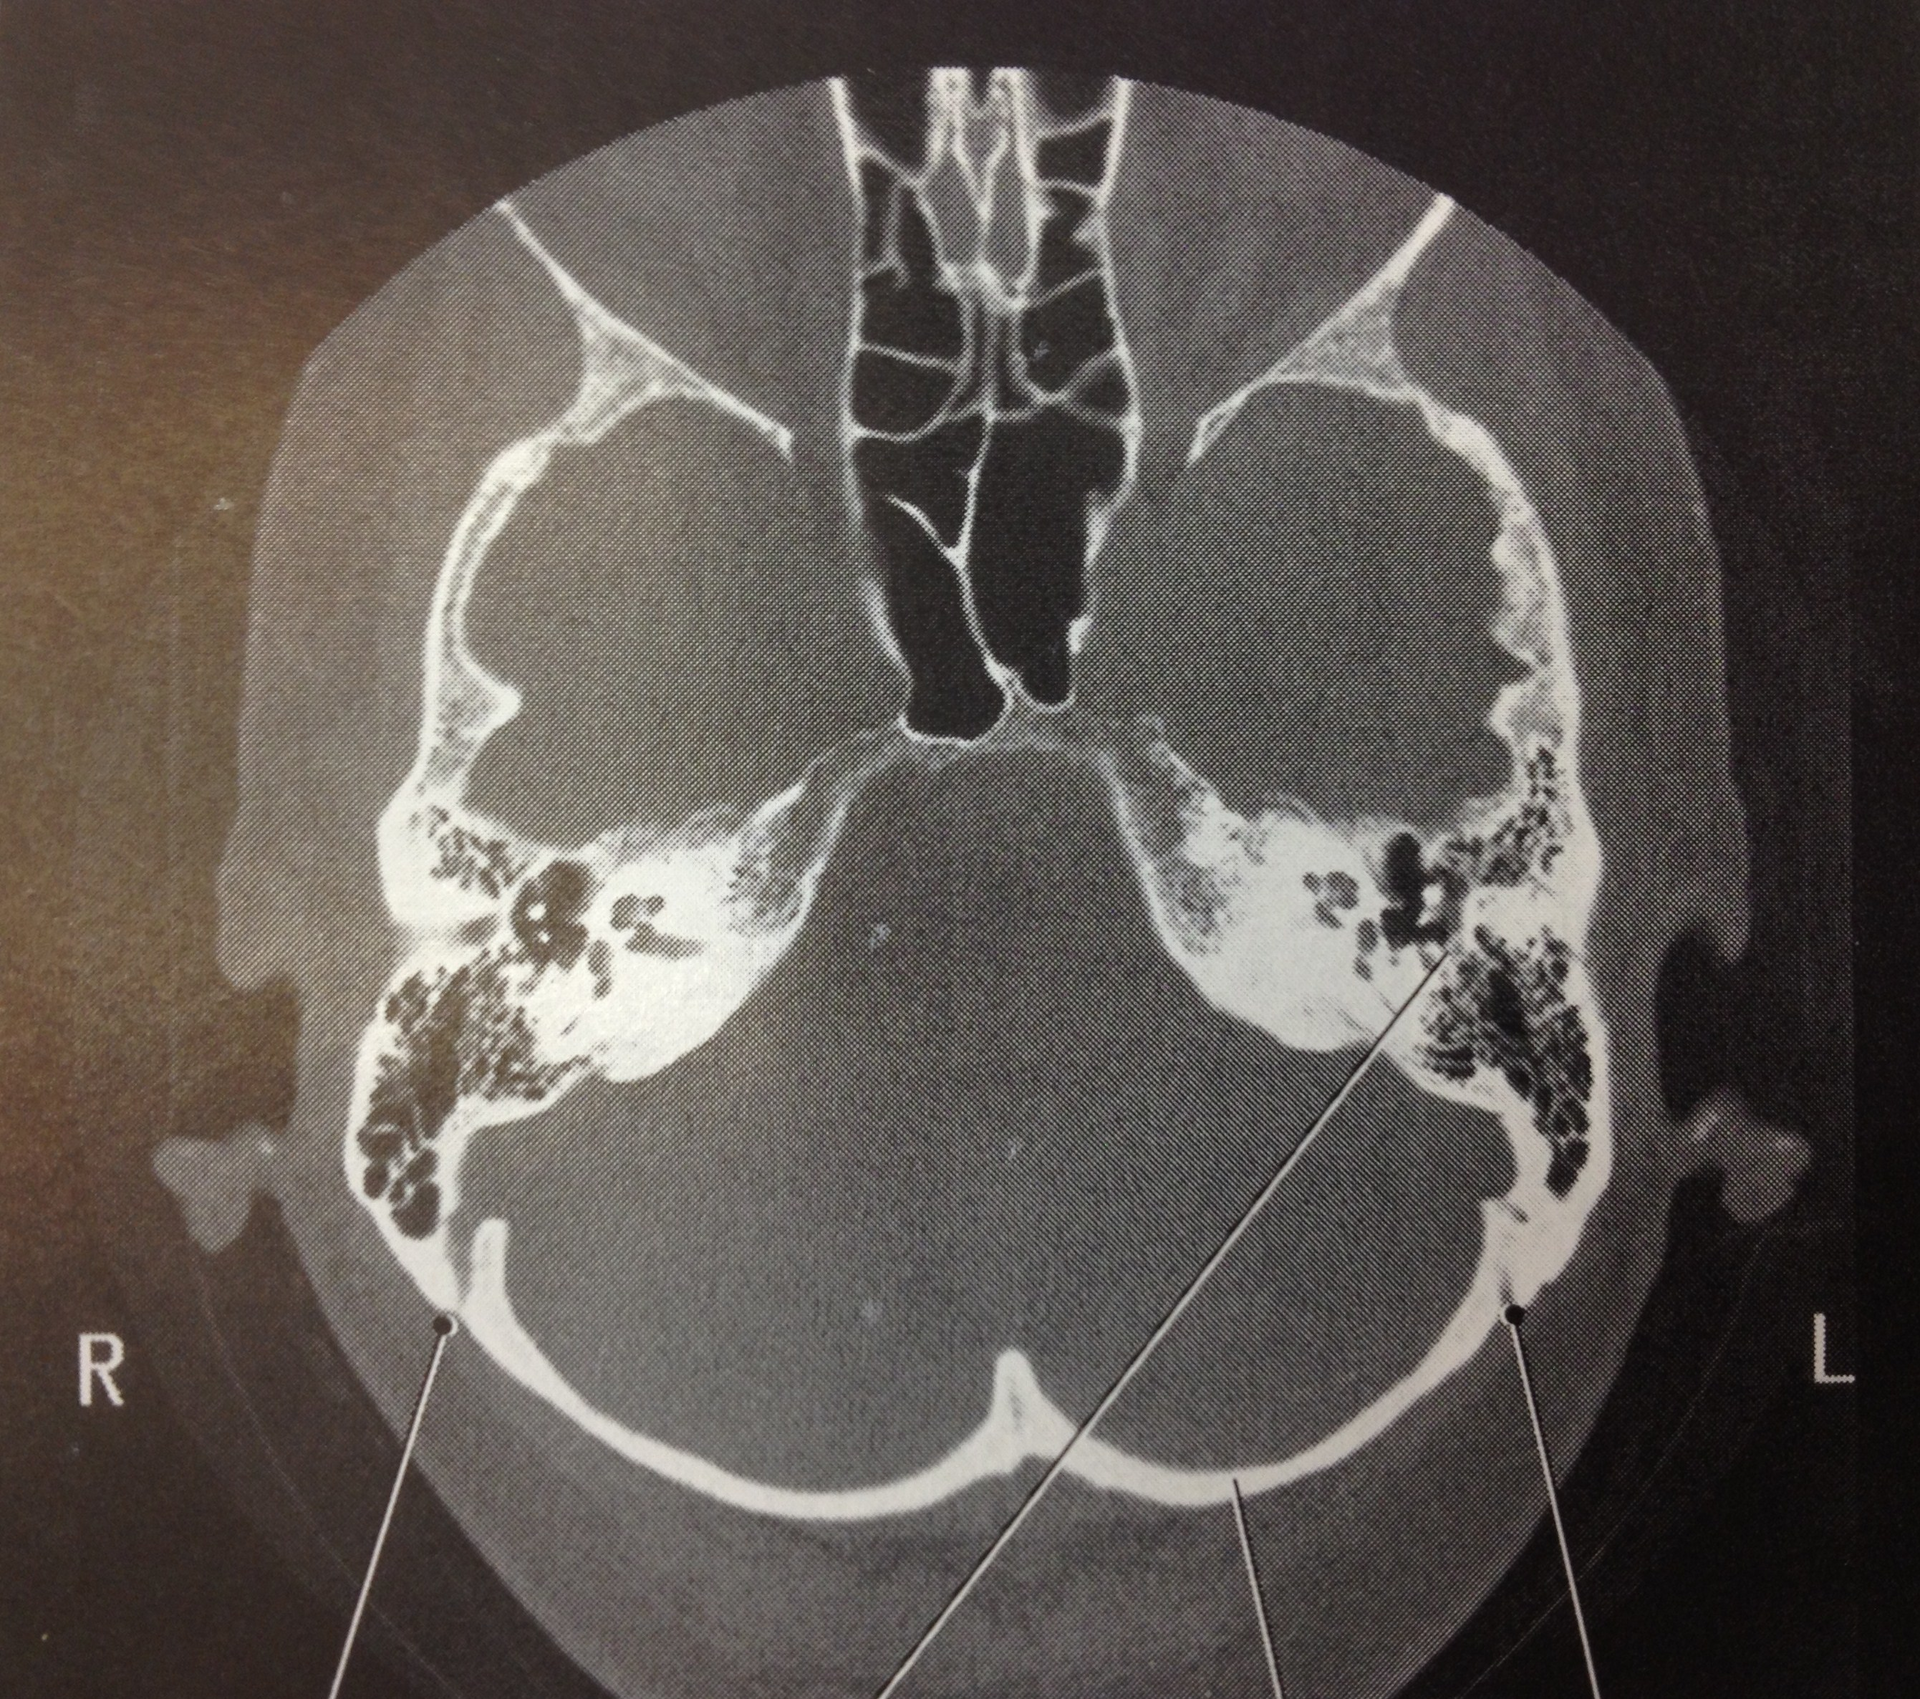

Imaging must be done to determine the location of the clot and whether the patient is a good candidate for thrombectomy, meaning they have a smaller area of brain tissue death. Physicians use non-contrast simple CT and/or CT with an injected contrast dye (CT perfusion) to view the clot and surrounding area of cellular death. While simple CT is readily available at most hospitals, CT perfusion tends to be only available at more advanced stroke centers.